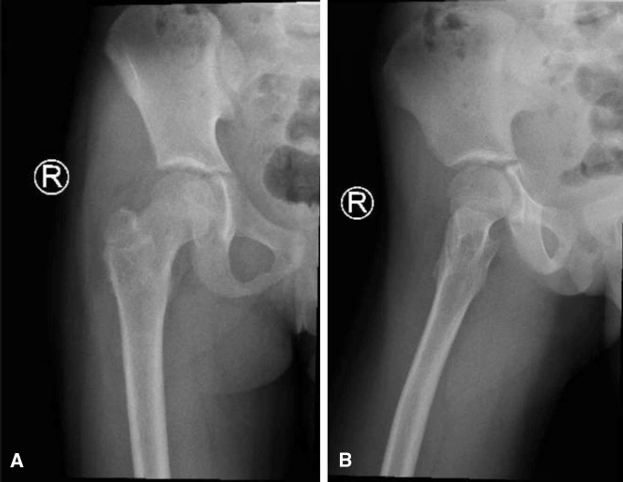

A. Anteroposterior pelvic radiograph showing a multiloculated osteolytic lesion in the right femoral neck extending from the growth plate to the intertrochanteric line, associated with cortical disruption (stress fracture) and varus displacement.

B. Frog-leg lateral radiograph confirming the same findings.